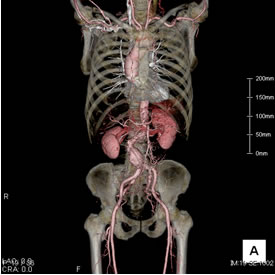

当院のMDCTで次のような画像を撮影することができます。